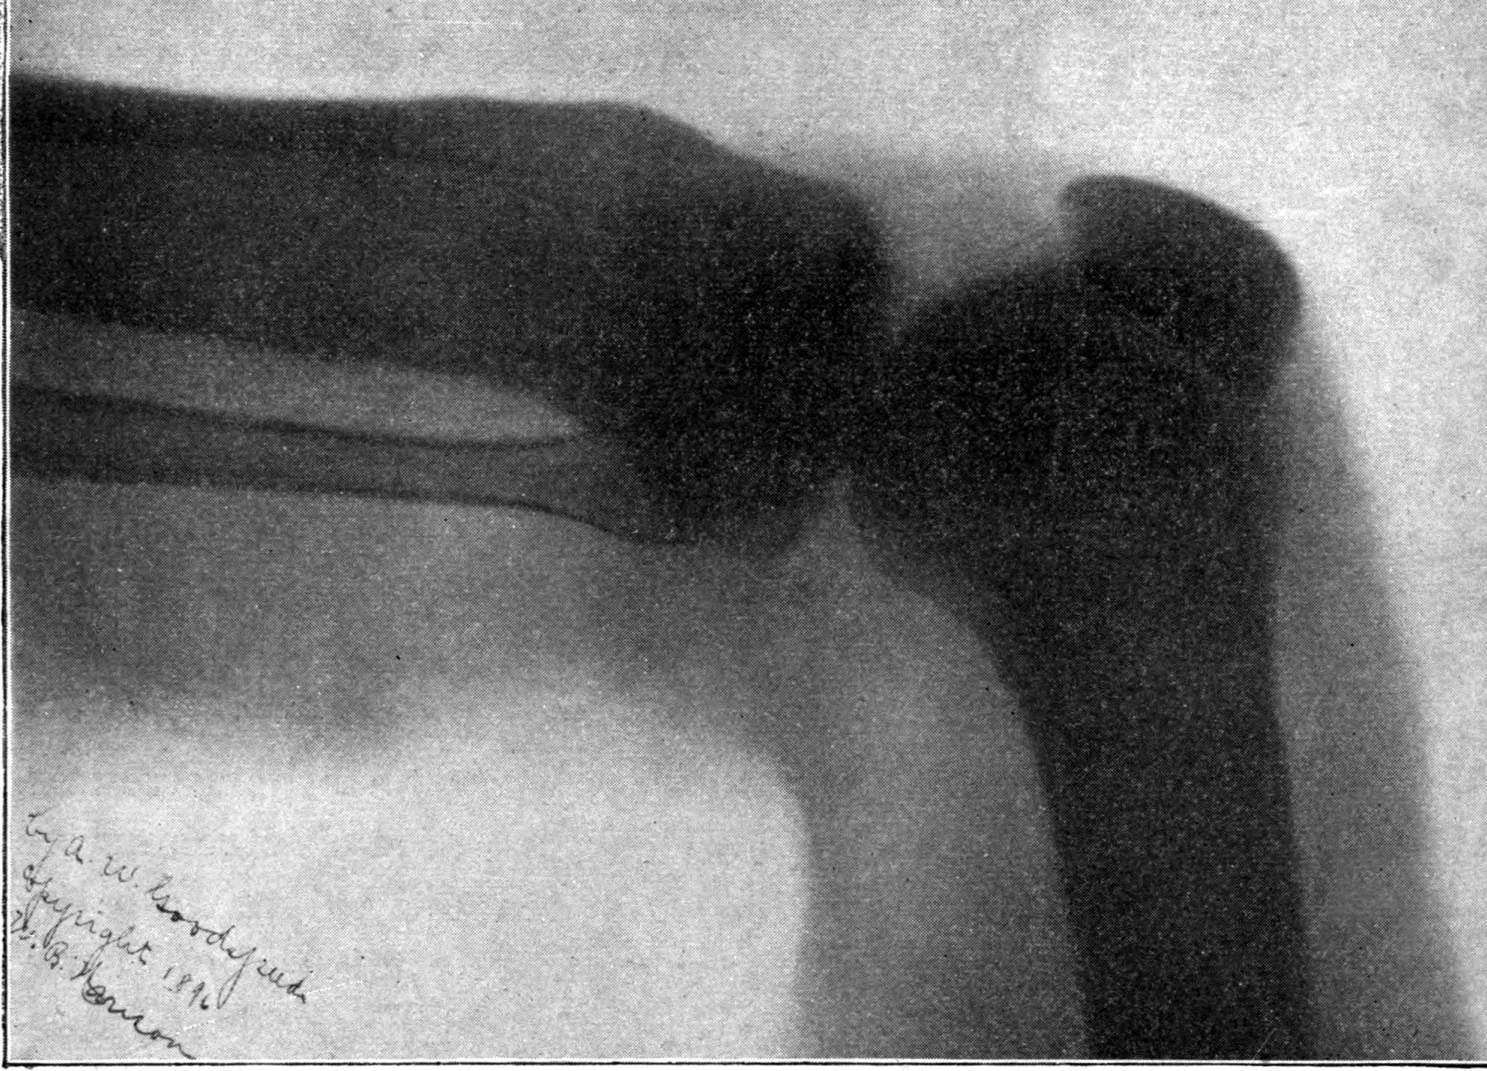

Fig. 2.—Broken Arm, Overlapping.

(Due to defective setting.)